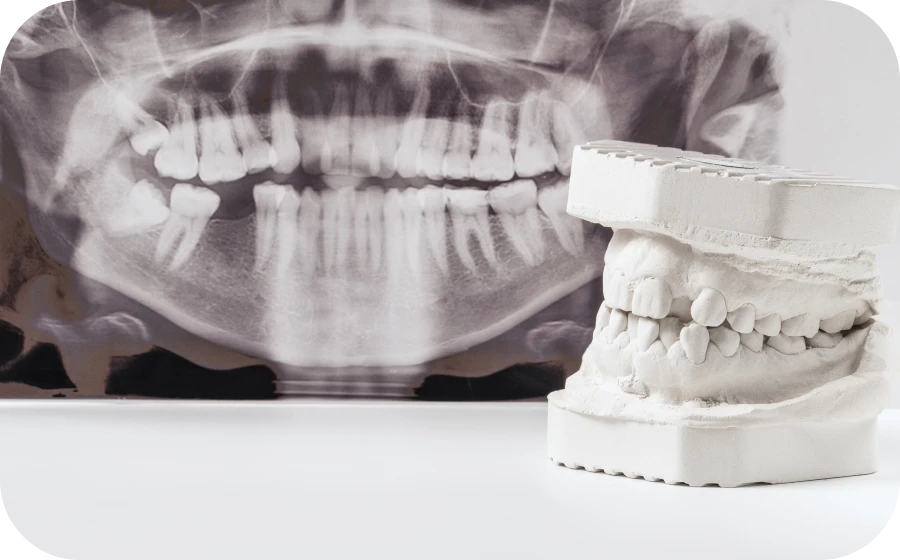

examen radiologique regeneration osseuse guidee tarare Régénération Osseuse Guidée (ROG) Centre d’implantologie des Teintureries

Un examen radiologique peut révéler une insuffisance osseuse. Celle-ci peut résulter d’une extraction ancienne, d’une infection chronique, d’une perte dentaire non compensée ou encore d’un traumatisme localisé.

Dans une telle situation, le chirurgien-dentiste propose une régénération osseuse guidée (ROG) afin de recréer les conditions favorables à l’implantation. Cette approche préventive réduit considérablement le risque d’échec implantaire.